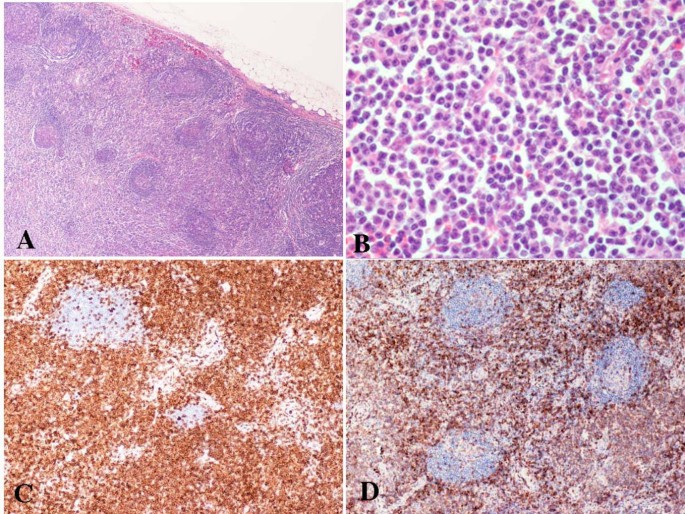

Вентрикуло-перитонеальный шунт: Показания и применение

Раздел: Фотоальбом решений